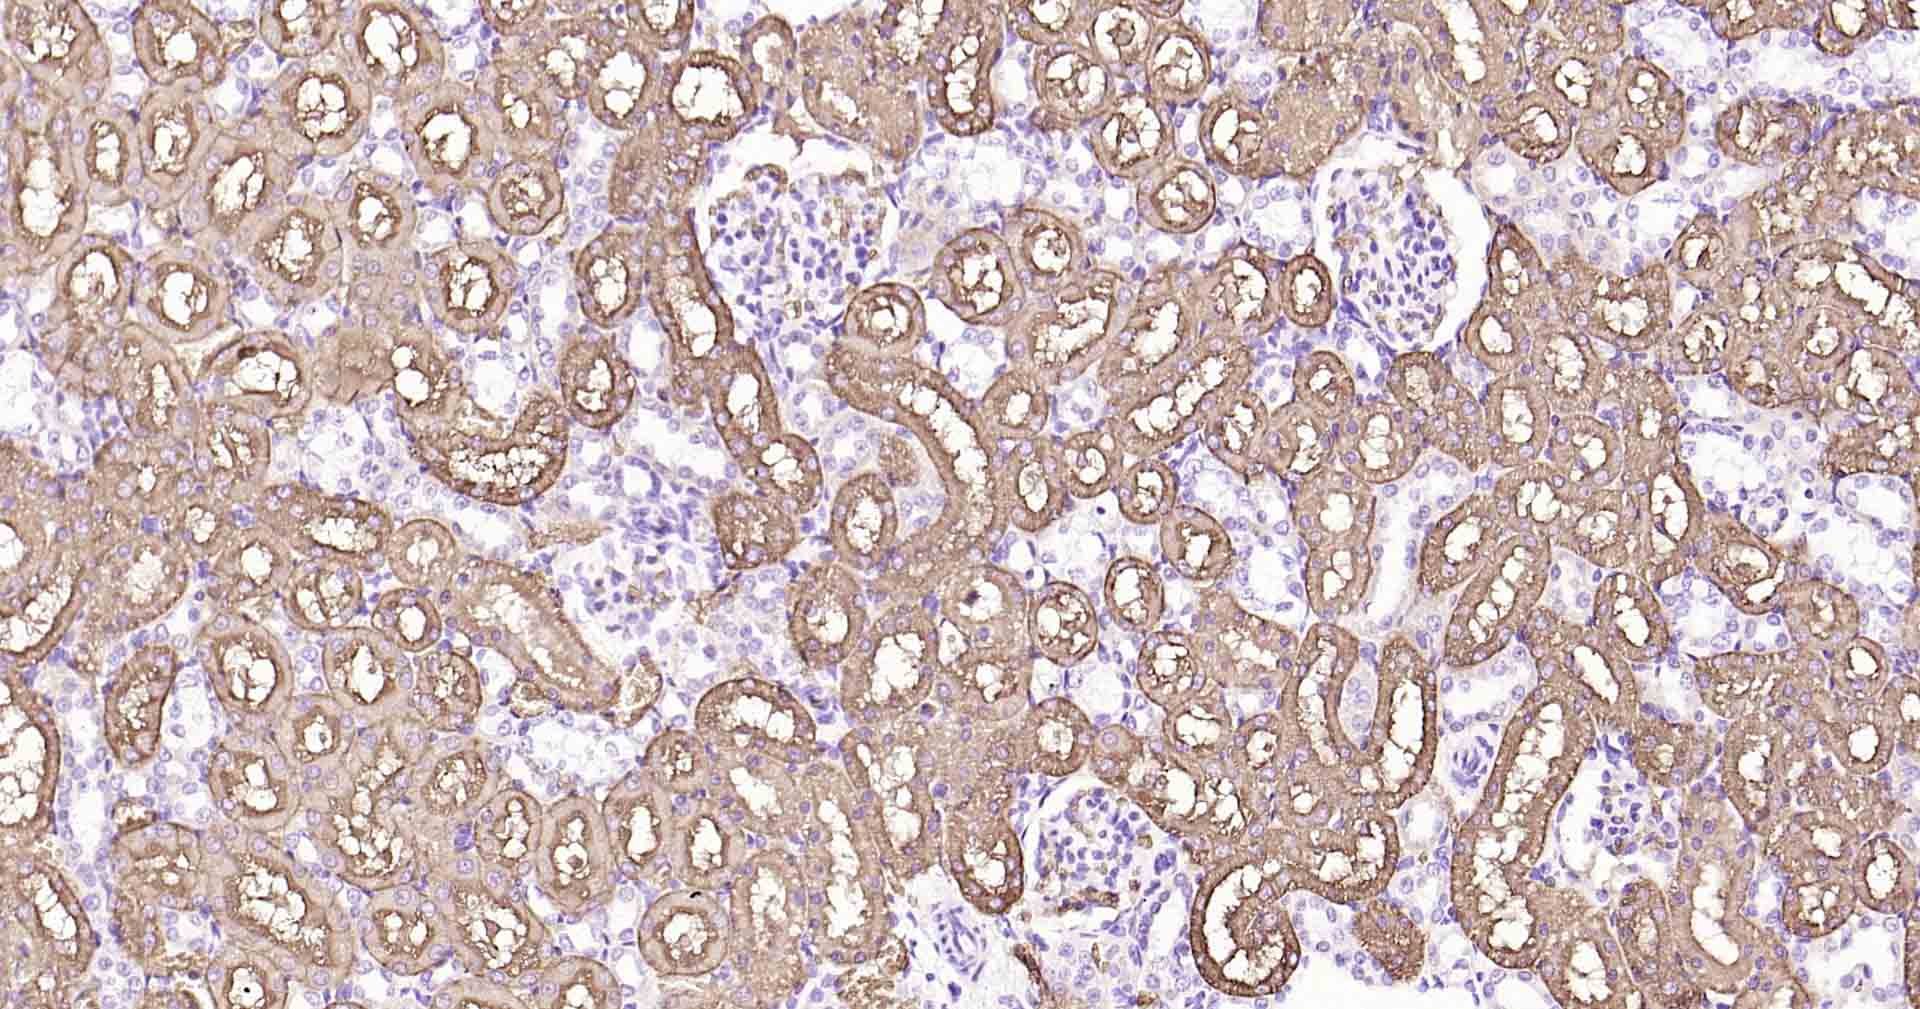

Paraformaldehyde-fixed, paraffin embedded Human Kidney; Antigen retrieval by boiling in sodium citrate buffer (pH6.0) for 15 min; Antibody incubation with AQP1 Monoclonal Antibody, Unconjugated(bsm-52909R) at 1:200 overnight at 4°C, followed by conjugation to the SP Kit(Rabbit, SP-0023) and DAB (C-0010) staining.

Paraformaldehyde-fixed, paraffin embedded Rat Kidney; Antigen retrieval by boiling in sodium citrate buffer (pH6.0) for 15 min; Antibody incubation with AQP1 Monoclonal Antibody, Unconjugated(bsm-52909R) at 1:200 overnight at 4°C, followed by conjugation to the SP Kit(Rabbit, SP-0023) and DAB (C-0010) staining.

Paraformaldehyde-fixed, paraffin embedded Mouse Kidney; Antigen retrieval by boiling in sodium citrate buffer (pH6.0) for 15 min; Antibody incubation with AQP1 Monoclonal Antibody, Unconjugated(bsm-52909R) at 1:200 overnight at 4°C, followed by conjugation to the SP Kit(Rabbit, SP-0023) and DAB (C-0010) staining.